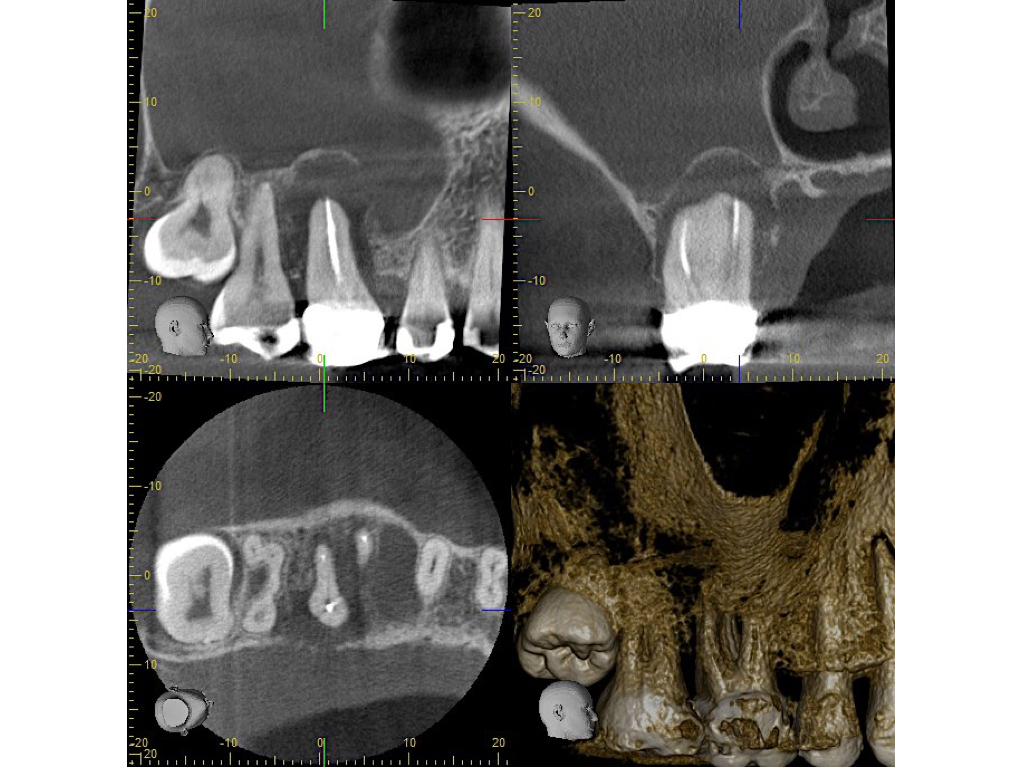

DVT Ausgangssituation